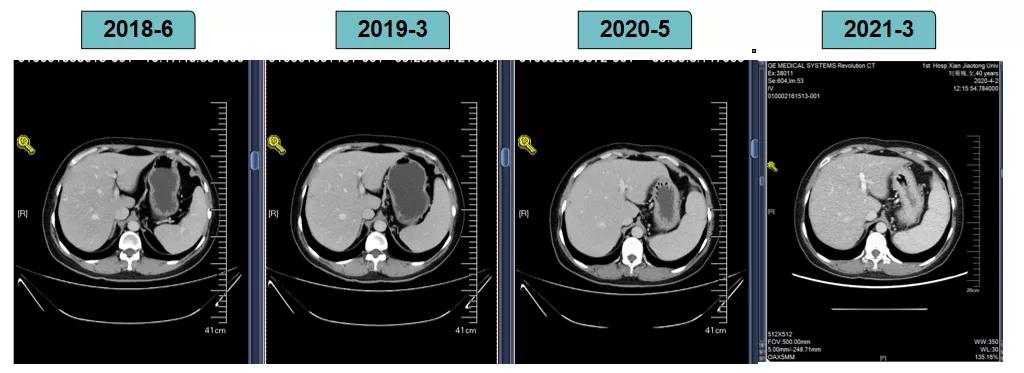

胸腹部增强CT示(2018-6-28):胸骨后占位,肝内异常强化灶,腹膜后肿大淋巴结。

非靶病灶:肝左叶、肝右前叶下段;纵膈胸骨后淋巴结节;前上纵膈淋巴结;腹膜后小淋巴结

影像学评估-肝脏: